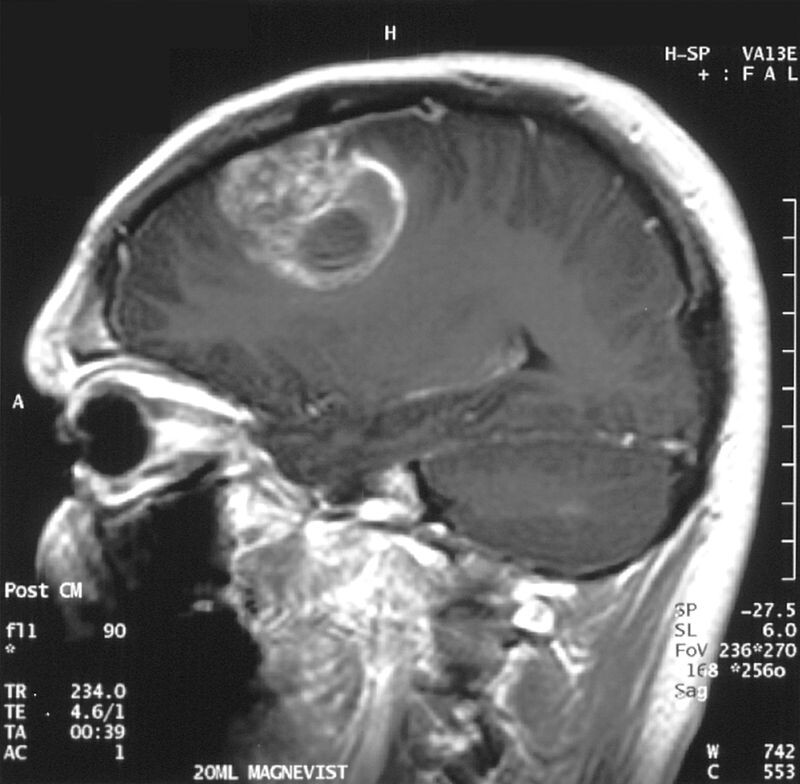

МРТ глиобластомы

Ученые из Университета Сент-Луиса (США) подводят к завершению слепое рандомизированное контролируемое испытание противоопухолевой вакцины DCVax-L. По предварительным результатам, исследуемая терапия улучшила показатели выживаемости пациентов, страдающих агрессивной глиобластомой. Данные опубликованыв Journal of Translational Medicine.